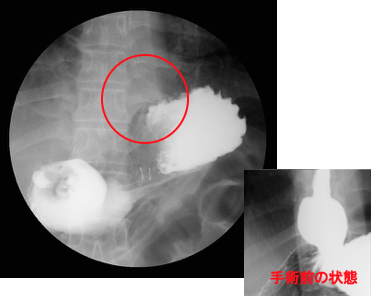

検査をすると、胃と食道の境目がゆるくて胃の一部が食道側に飛び出し(図1)、(図2)。一度胃に入ったバリウムが食道に戻ってきます(図3)。

検査中もバリウムが食道内へと逆流してきます。

胃の中から、胃の入り口を見上げた写真です。本当は締まってなくてはいけない胸とお腹の境い目が大きく開いています。